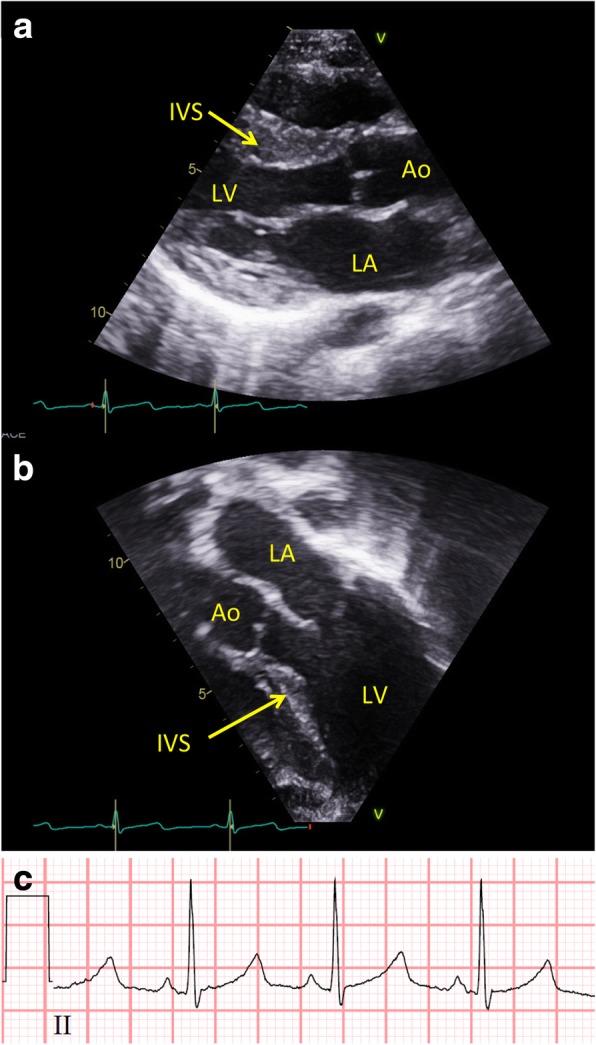

Patient 2 is the second child to non-consanguineous parents. He was born after 39 weeks of gestation. Birth weight 3344 g (median), length 51 cm (median), and head circumference 36 cm (+1SD). He had neonatal-onset hypotonia and poor feeding. He was breastfed to some extent until he was five years old. He presented with developmental delay at 12 months. Early milestones: he sat at 6 month, walked at age 2 years 3 months, from 18 months he rolled around indoors. He had very poor speech development and only uses a limited number of words with 2–3 worded sentences aged 12 years. He has behavioural issues including poor concentration, but is a quite happy and very active boy. He had eczema and very fine and sparse scalp hair until 3 years of age. He has a tendency to develop mild fevers of unknown origin. He does not have epilepsy. His height has been constantly at -2SD since 2 years of age; at 12 years his height was 142 cm. Dysmorphic features at 12 years of age was rather mild in the form of large ears, and rather closely spaced eyes. Cardiac examination revealed a structurally normal heart, i.e. no congenital malformations. Measurements of ventricular wall thickness were taken at end-diastole, indexed to body surface area and z-score measurements calculated as described by the Pediatric Heart Network [62]. This revealed a predominantly septal hypertrophy (z-score + 8.3) and reduced end-diastolic diameter of the left ventricle (Fig. 1). Although the septal hypertrophy caused narrowing of the left ventricular outflow tract, it did not cause obstruction to flow (Fig. 1 A and B, Additional file 1: Video S1). The ECG was normal except for borderline prolongation of the corrected QT-interval (420 milliseconds, Fig. 1 C). To assess for potential arrhythmias a 48-h Holter monitoring was performed. The heart rate varied between 66 to 165 bpm, and on average was 106 bpm. No arrhythmias were detected. Trio exome sequencing revealed a mosaic de novo NAA10 ((NM_003491.3) c.248G > A, p.(Arg83His)) hemizygote missense variant, with a mosaic degree of 75%. The variant was confirmed by Sanger sequencing.

Fig. 1.

Cardiac hypertrophy in patient 2. Transthoracic echocardiography showing the left ventricle in a parasternal long axi and b apical 3-chamber view. Please note how the hypertrophy predominantly affects the interventricular septum with relative sparring of the apical and posterior regions. Red marker on EKG trace shows temporal relation to heart cycle. LV, left ventricle; Ao, aorta; LA, left atrium; IVS, interventricular septum. c Standard electrocardiogram (EKG) in patient 2. Note the borderline prolonged QTc

Video S1. Transthoracic echocardiography showing the left ventricle from an apical 3-chamber view (identical to Fig. 1) during two heart cycles in color compared mode. Please note that although there is no obstruction to flow in the left ventricular outflow tract (LVOT), a slight turbulence does occur along where the hypertrophic septum protrudes into the LVOT. (MOV 793 kb)